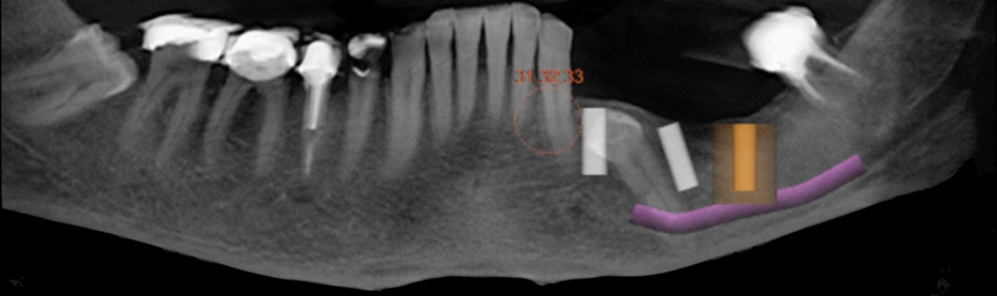

Case 4: a 38-year-old patient presented a class III maxillomandibular relationship with retention of multiple permanent and supernumerary impacted teeth. The teeth in the mouth were deciduous, supernumerary. Due to the number of impacted teeth and the size of the roots of the teeth in the mouth, orthodontics was contraindicated. Initial treatment was performed using Le Fort I osteotomy for maxillary advancement and bilateral sagittal osteotomy of the mandibular ramus for setback (figure 13). After 6 months under general anesthesia, the teeth in the mouth were removed, and 4 implants were installed in the maxilla and 4 in the mandible, respecting the remaining included teeth with the exception of the implant installed in the region of tooth 21 that transfixed the crown of the one that was included.

Two protocol-type prostheses in immediate loading were installed. In the 18-month control, prosthetic normality was observed and in the imaging examination, normality was observed in the 8 implants and the remaining impacted teeth (figure 14).

Figure 13: Panoramic radiograph after the period of implants osseointegration and prosthetic rehabilitation.

Figure 14: Panoramic radiograph after performing maxillary advancement and bilateral sagittal osteotomy of the mandibular ramus for setback

Case 5: a 62-year-old patient with a complete denture sought treatment with osseointegrated implants seeking a fixed prosthesis. In the imaging exams, it was observed that the upper left canine was included in a vertical position, extending from the midline to approximately tooth 24 (figure 15).Six implants were installed, with the most anterior fixation of the left maxilla being installed by milling the impacted tooth on purpose. After 90 days of osseointegration, the implants were reopened and a protocol-type prosthesis was made. After 18 months of function, no type of clinical or radiographic change was found about the implants or the impacted tooth, nor were any prosthetic complications found (figure 16).

Figure 17: Panoramic radiograph after the period of implants osseointegration and prosthetic rehabilitation.